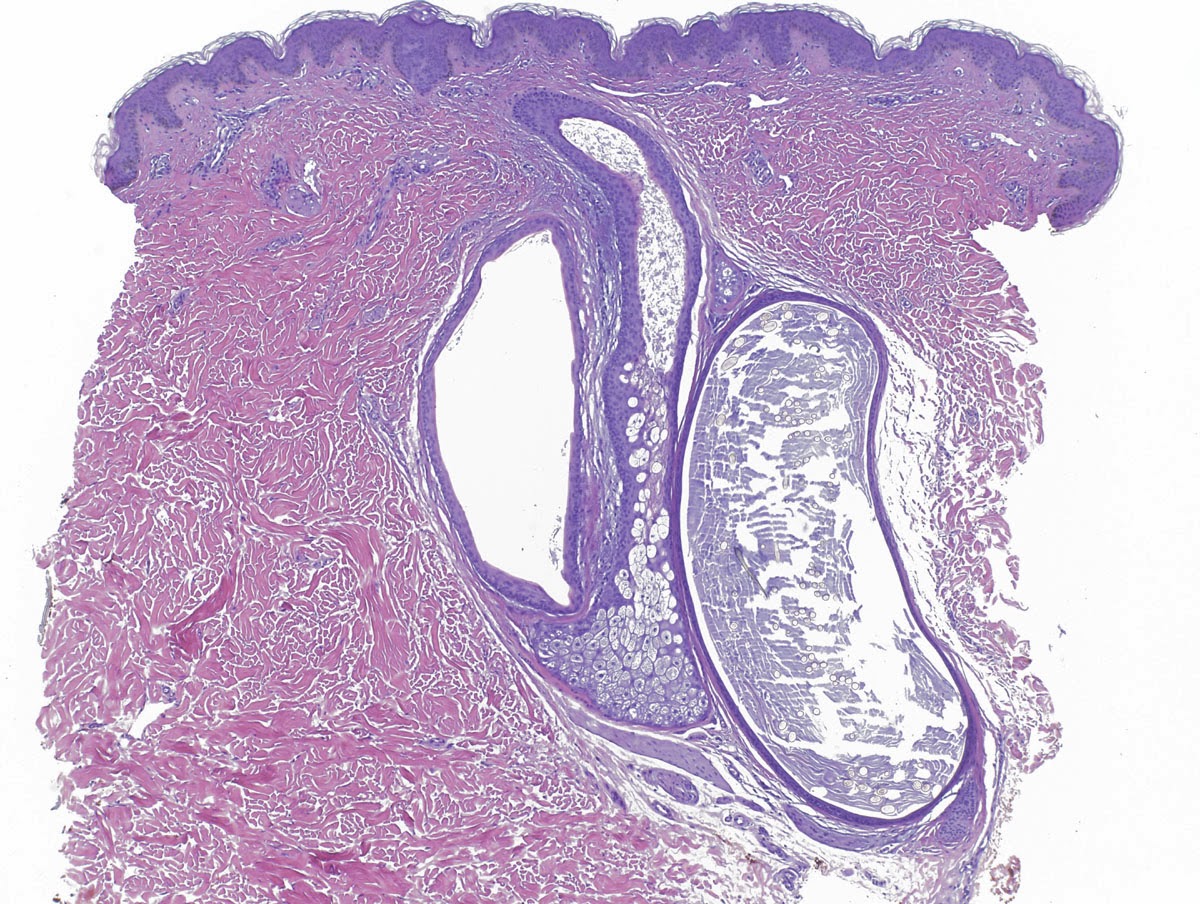

Vellus hairs present in cysts from clinical presentation case 1, a Vellus Hair Causing Acne They are usually seen in. eruptive vellus hair cyst (evhc) is a rare follicular developmental abnormality of the vellus hair follicles. the sebaceous follicles (located on most of the face and where most acne occurs) only have tiny vellus hairs, are prone. It is not related to vellus hair transplant, which is. It feels smoother and is less. Vellus Hair Causing Acne.